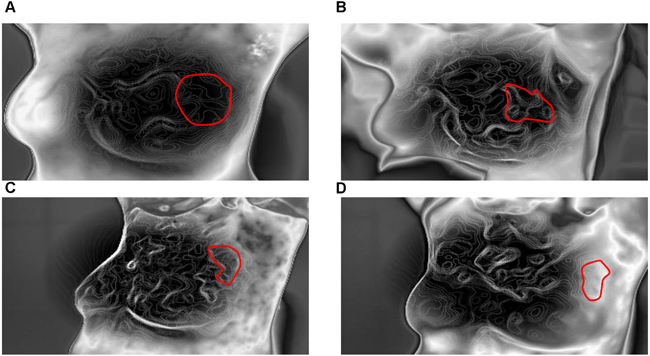

Figure 1: Thermal tomography images of a typical response before and after NAC. A.-D. show a significant decrease in surface temperature in the area of the tumor before and after one, three, and six cycles of NAC (these measurements can vary from black (coolest) to white (warmest), with 14 “intermediate” colors).

Furthermore, the values relative to baseline were adopted to intuitively assess trends. However, based on pathologic criteria, the relative ΔTs, ΔTn and ΔTa values shown in Table 2 significantly differed between the responding and nonresponding groups after 1 cycle of NAC (P < 0.05). The q-r curve relative to baseline also indicated a significant decrease. Due to their subjective nature, it is difficult to evaluate diagnosis based on blood vessels and isothermals, though changes can be assessed from TT images. Figures 1, 2, 3, 4 show representative TT images of the response group during NAC therapy (TT images are shown in Figure 1A-1D; q-r curves are shown in Figure 2A-2D; blood vessel scans are shown in Figure 3A-3D; and isothermals are shown in Figure 4A-4D). After three and six cycles, the ultrasonography measurements of cross-sectional areas significantly differed between the responding and nonresponding groups (P < 0.05; Table 2). In addition, the sizes of the tumors on scans decreased after NAC in both groups.